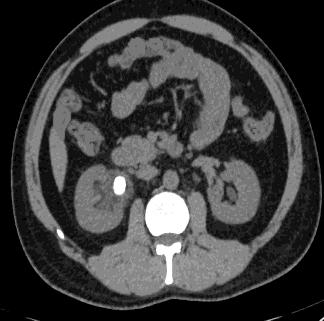

Fig6 CTexaminedpictures

Bringinginthepicturethroughpicturesecuringapparatuses;Breakingdownandcontrollingthepicture;Outputin whichresultcanbeadjustedpicture.

ImagePre processingisacommonnameforoperationswithimagesatthelowestlevelofabstraction.Itsinputand outputareintensityimages.

The point of pre handling is an improvement of the picture information that stifles undesirable contortions or upgrades somepicturehighlightssignificantforfurtherprocessing.